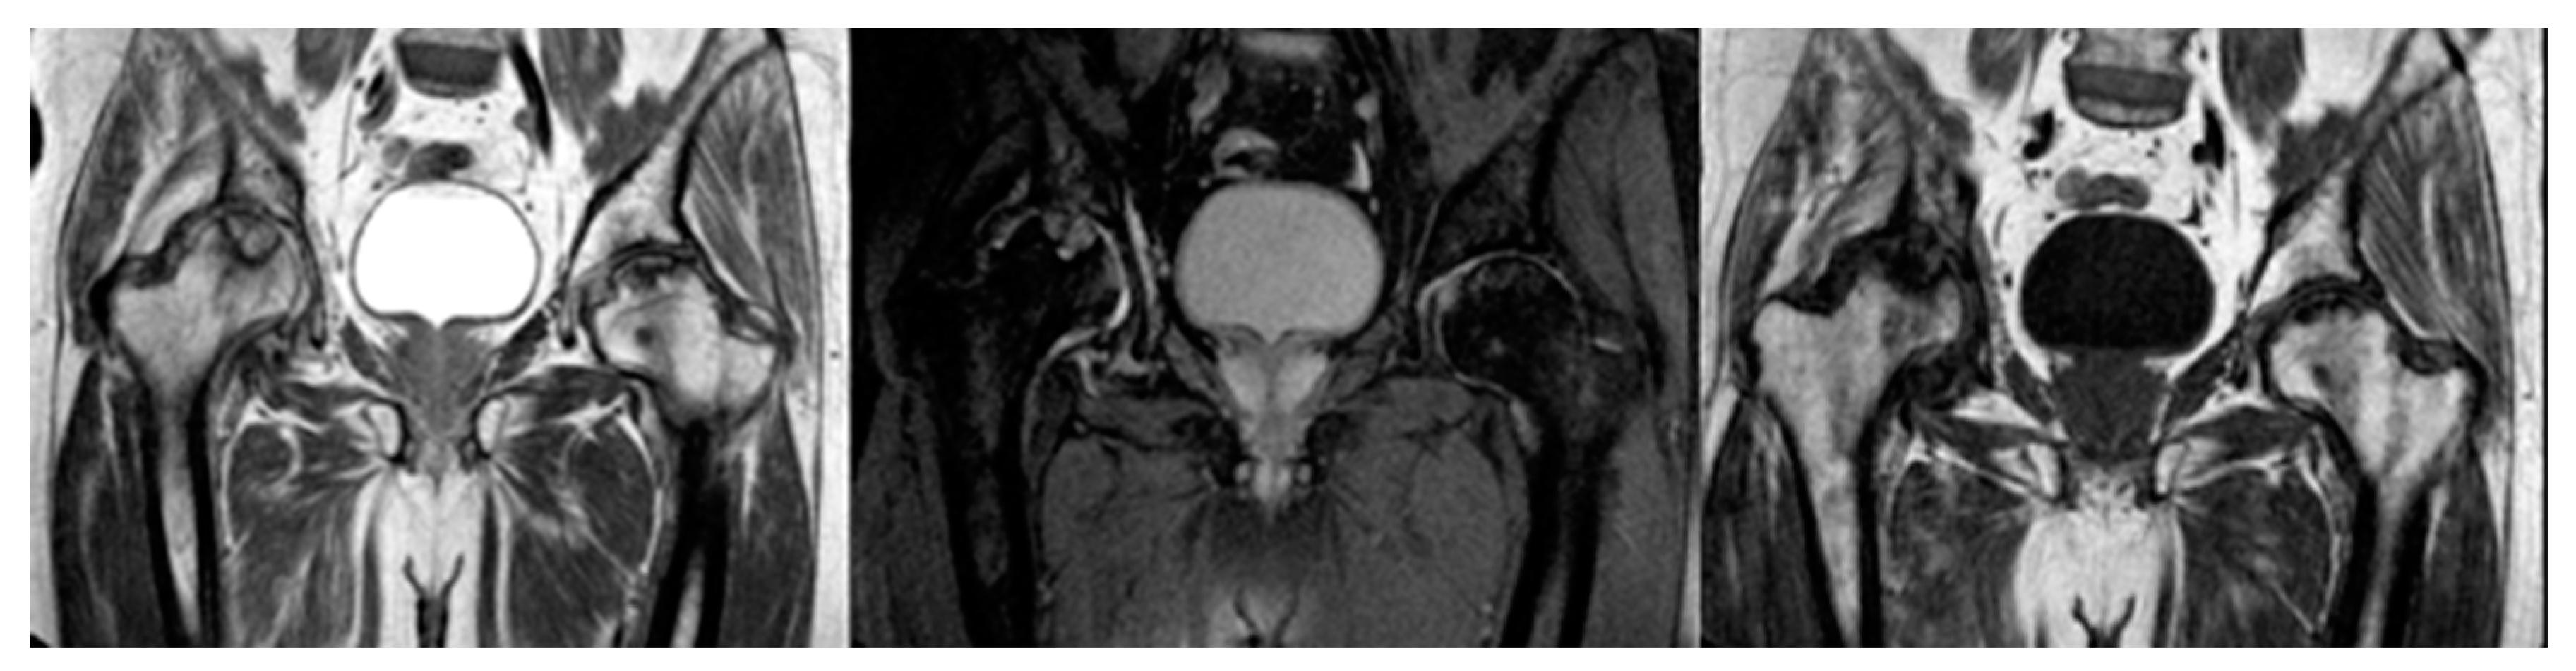

Figure 2. Treatment of AVN with Total Hip Arthroplasty.